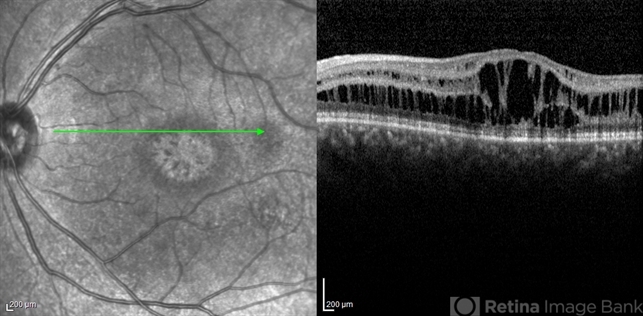

- optical coherence tomography (OCT), juvenile retinoschisis, macular schisis

- Shabnam Pooreh, Negah Eye Center, Tehran , Iran

Optical coherence tomography system

Specteralis - Description

- OCT image of the left eye of a 30-year-old man with juvenile retinoschisis. VA OS is 20/100.